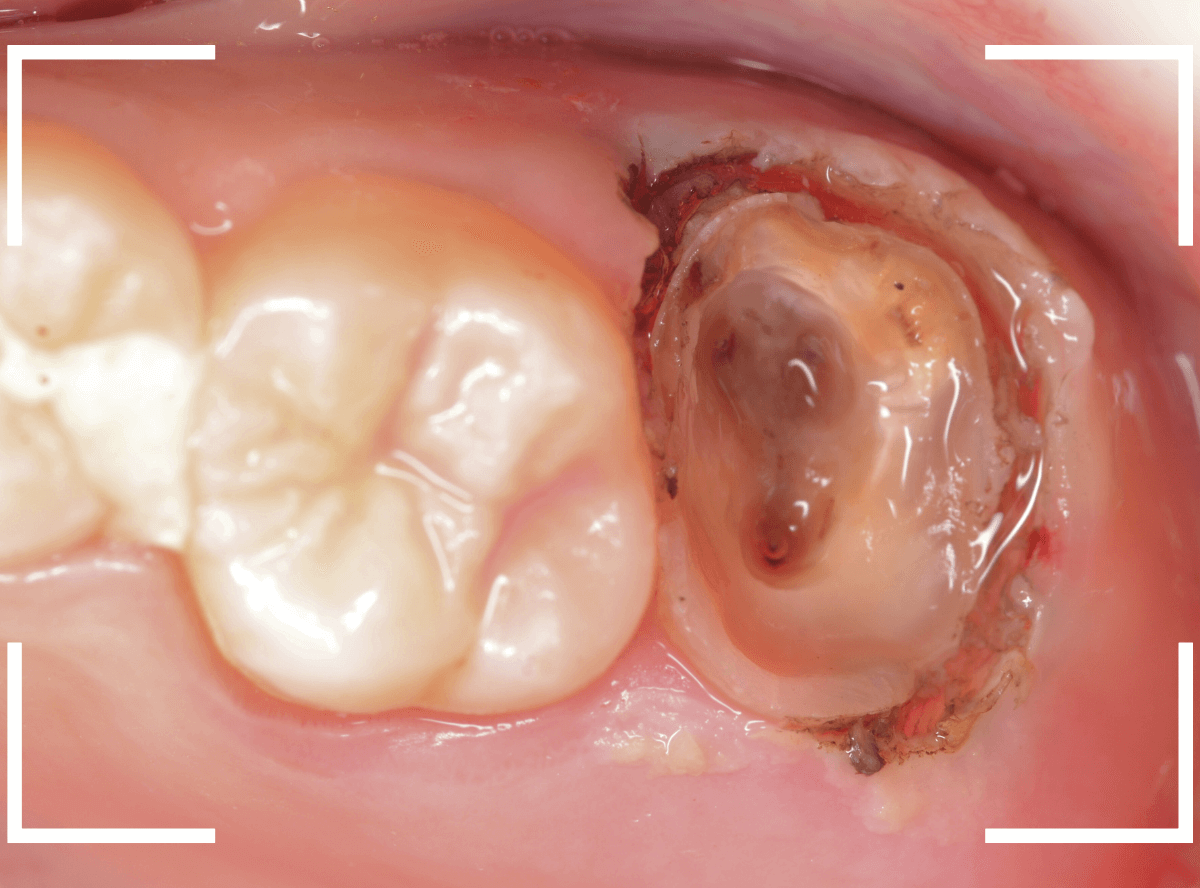

このように歯の際が歯肉からしっかり出てる状況で製作しないと、さし歯はしっかりお口の中で安定しません。

この状態で新しい土台(ファイバー・コア)の型を取ります。

模型上でファイバーコアを製作します。

ファイバーコアをsetし、歯の周りの歯肉が落ち着くまで、仮歯を入れて様子を見ます。

頃合いをみて、歯の型をとってさし歯の製作に移ります。

今回は、オール・ジルコニア・クラウンで製作することになりました。